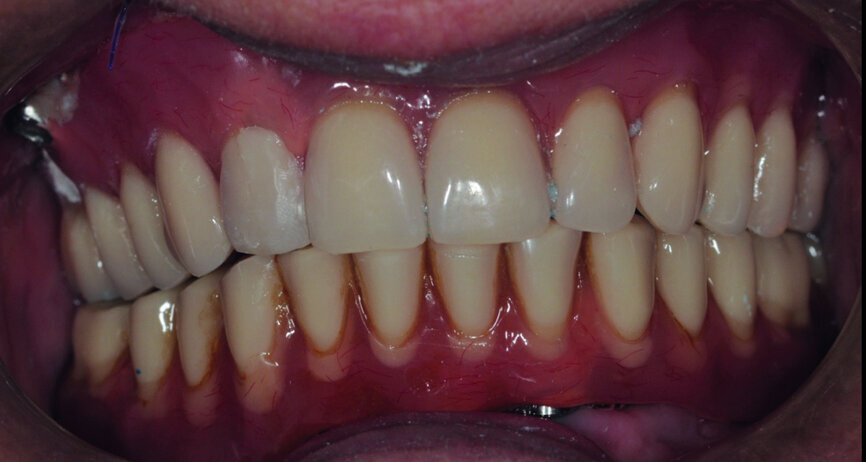

Fig. 7 : Bridges terminés.

Cette technique permet ainsi de se dédouaner des variations dimensionnelles liées à la coulée métallique (Figs. 4 et 5).7 Le plus souvent, le prothésiste dentaire utilise au sein du laboratoire et en fonction du montage esthétique préalable, des préformes calcinables « direct implant », sans bague de collage. La fausse gencive maquillée et les dents en résine seront montées classiquement. La mise en place finale est facilitée par le vissage à plat. Ce bridge de transition est de conception définitive, il peut donc être laissé en place. Dans certains cas où l’exigence esthétique prime, il peut être remplacé au bout de douze à dix-huit mois par un bridge d’usage définitif. Le protocole est identique à la mandibule comme au maxillaire.

Le bridge transitoire de forte rigidité vissé passivement, nous semble être une bonne réponse au cahier des charges de ce type de traitement, pour le chirurgien-dentiste comme pour le prothésiste dentaire. Utilisée pour une mise en charge immédiate, cette technique évite le port d’une prothèse amovible transitoire ainsi que la chirurgie de réouverture.